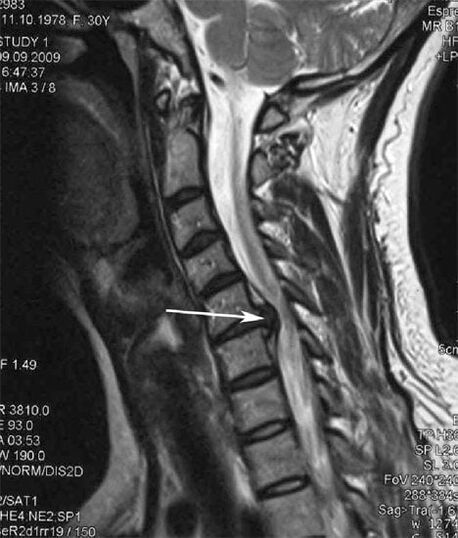

In de beginfase wordt osteochondrose gedetecteerd met behulp van MRI. Later kan pathologie worden gediagnosticeerd met behulp van radiografie. Op röntgenfoto's van de cervicale wervelkolom worden een afname van de afstand tussen de wervels, pathologische veranderingen in de facetgewrichten en osteofytose merkbaar.